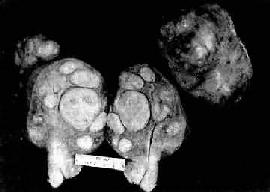

图13-7 子宫平滑肌瘤

多个肌瘤结节,位于肌壁内、粘膜下及浆膜下,境界分明,宫腔受挤压呈裂隙

肉 眼观,肌瘤可以生长在子宫任何部位,常位于子宫壁内(肌层内肌瘤)、浆膜下(浆膜下肌瘤)或粘膜下(粘膜下肌瘤)。可单发或多发,常为多个,其数目多少不 等,常见为数个、乃至十数个或数十个,称多发性平滑肌瘤。肌瘤的大小可极为悬殊,小的在显微镜下才可检见,大的如成人拳大或更大,甚至可充满整个腹腔。肌 瘤多呈球形或融合成不规则形,质较硬,界限明显,但无明显包膜(图13-7)。切面上,瘤组织常呈灰白色,编织状或旋涡状,当肌瘤生长较快或供血不足时, 可发生各种继发性改变,如玻璃样变、粘液变、囊性变、水肿出血坏死等。